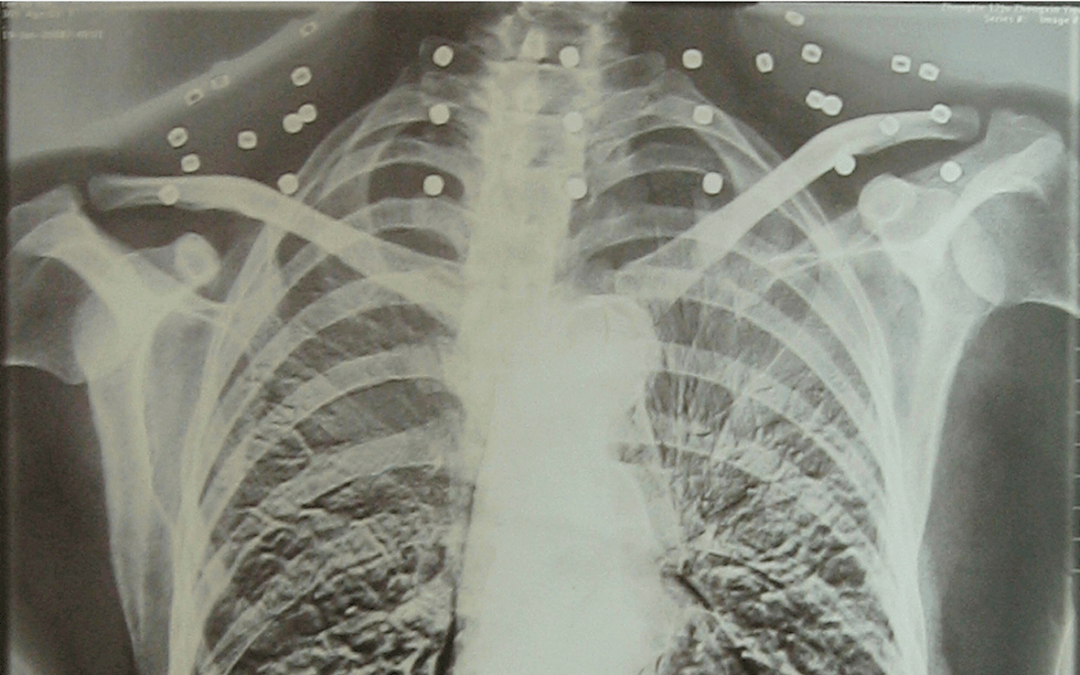

这张照片

是今年82岁的吴以先老人

拍摄的一张CT照

吴以先的颈部和腹部

共分布着33枚弹片